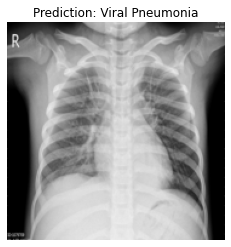

Currently, there is an urgent need for efficient tools to assess the diagnosis of COVID-19 patients. In this project, we propose a constructive solution for detecting and labeling infected tissues on CT lung images of such patients. To cut down false positives our model is trained on 4 types of lung CT images : COVID, Viral Pneumonia, Lung Opacity and normal images to get the best possible results with highest accuracy.

We built it using Tensorflow 2.x using Python. We have developed a Convolutional Neural Network model with an average accuracy of more than 85%. We built the WebApp using Streamlit library for easy interaction with the prediction model.

We are proud that among the top 5 models, one of our models achieved 88.8% accuracy with very low loss.